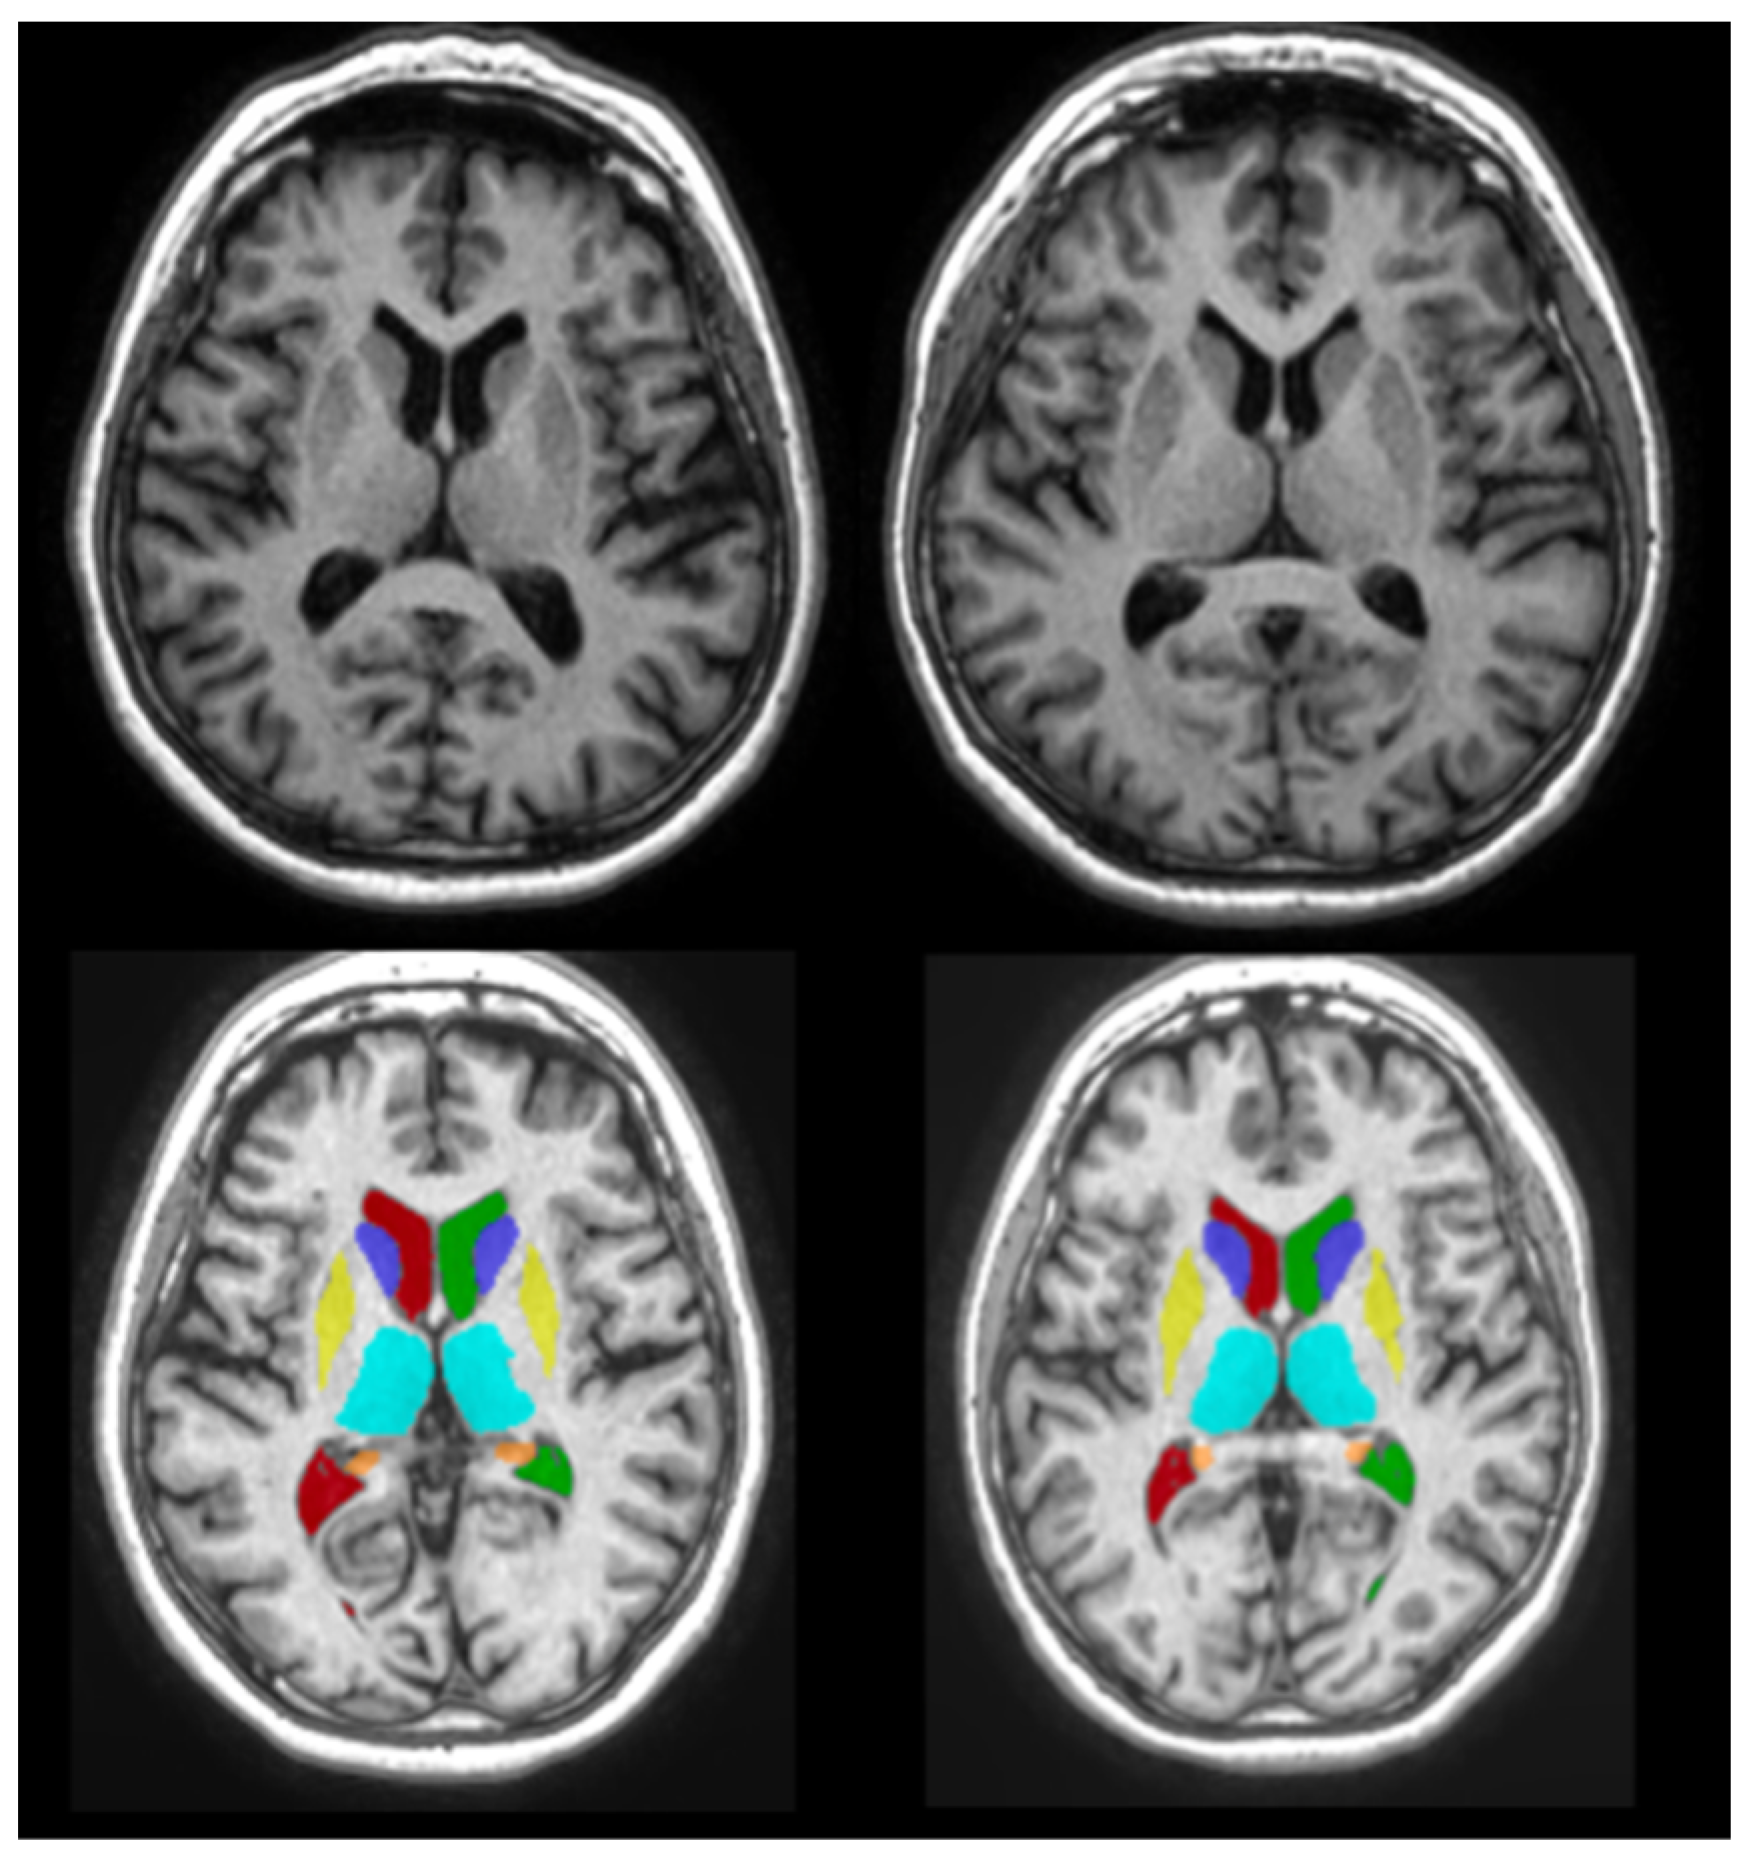

2.3.2. Volumetric Measurement Using volBrain